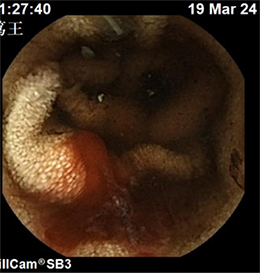

下图可见小肠内新鲜活动性出血